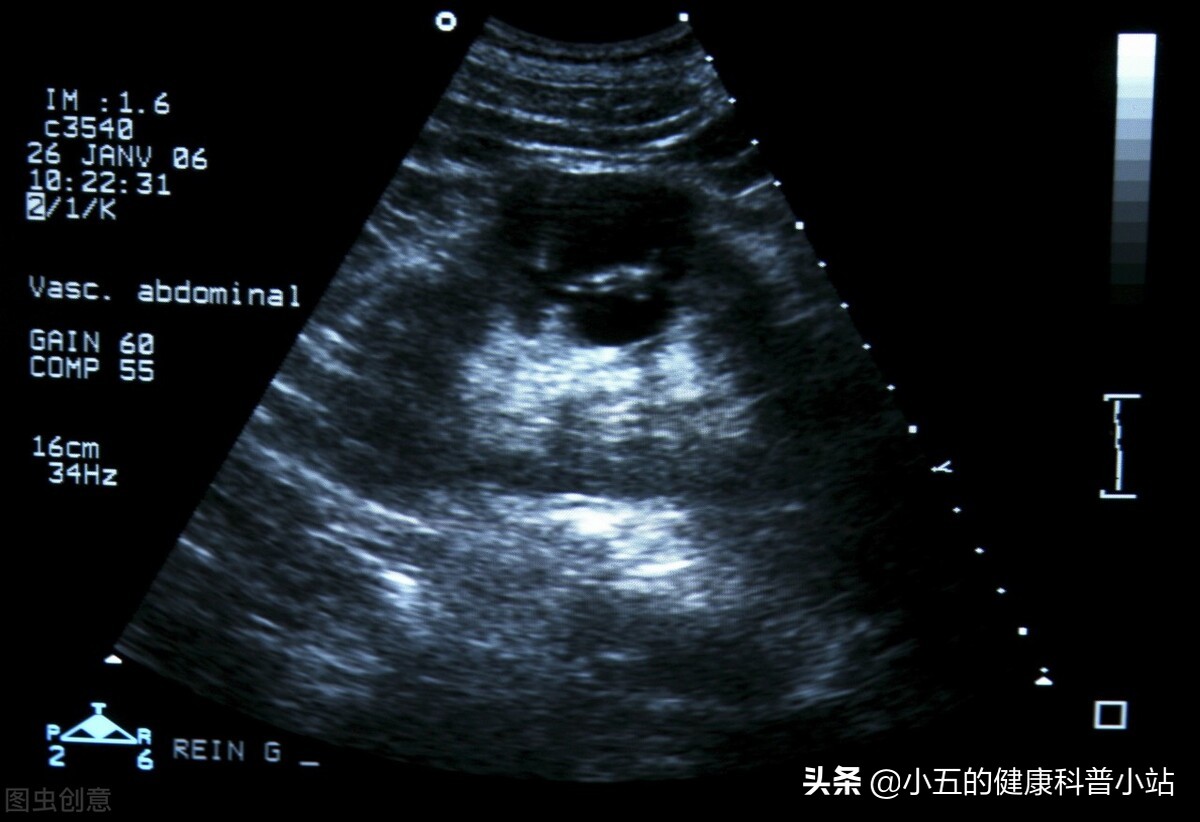

医生通过给小陈进行了泌尿系彩超和尿常规检查后, 诊断为肾结石、肾囊肿 ,原因就是小陈平时饮水太少,并且不能及时去厕所导致。肾结石小陈听过,毕竟这是他们这一行惯有的病,肾囊肿是第一次听说,连忙问大夫肾囊肿是什么?是肿瘤吗? 医生解释道肾囊肿其实囊性病变,就像肾里张了“一泡水”,并不是恶性病变 ,小陈的肾囊肿只有2cm大小,对肾功能影响不大, 但如果不进行干预,不排除会逐渐变大,直至导致严重肾功能衰竭 ,于是建议在改善自己的生活习惯的同时,定期复查肾脏彩超,关注肾囊肿的变化,小陈答应了。

肾囊肿是常见的肾脏异常结构, 是指肾脏内出现大小不等、封闭的液体或半固体结构的囊性包块 ,根据大小和特点可以分为 多囊肾、单纯性肾囊肿、获得性肾囊肿 等多个类型,其中临床最常见是单纯性肾囊肿。

肾囊肿可以发生在任何年龄,其中50岁以上的中老年人多见。肾囊肿的形成时间较长,而且 早期临床症状并不明显,许多人是在行彩超检查或者CT检查时才发现 ,但如果肾囊肿发生破裂或者体检明显增大时,就会导致许多临床症状,其中腰痛、血尿、发热等最为常见,许多人容易与尿路感染相混淆。